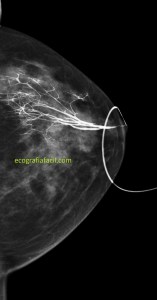

En el caso que te presento hoy, una mujer, que se realiza una revisión ecográfica mamaria por seguimiento de una lesión nodular en la mama izquierda a expensas de una mamografía, imagen 1, donde se observa en cuadrantes superiores una lesión nodular marcada con flecha amarilla.

Cuando realizamos la ecografía objetivamos un nódulo en la región donde teóricamente tendría que estar el nódulo visualizado en la mamografía. Hasta aquí todo genial, el problema es que las dimensiones del nódulo de la mamografía y el de la ecografía son demasiado diferentes y por tanto no concordantes.

La paciente tiene una mancha en la línea intercuadrántica externa de la mama a estudio, coincide en tamaño y posición con el nódulo mamario. Normalmente las lesiones cutáneas objetivadas en mamografía son debido a verrugas o lunares voluminosos, en este caso la casualidad hizo coincidir un nódulo en la mama con la misma localización (imagen 2) de una lesión cutánea que, normalmente no vemos con el estudio ecográfico, pero esta, por su profundidad me llamó la atención y la radióloga recomendó estudio por parte del servicio de dermatología del hospital para caracterización.

1

Si te fijas en la imagen, la lesión mamaria es un nódulo evaluado por la radióloga con aspecto de benignidad, redondeado, buena transmisión de sonido, bordes bien definidos.